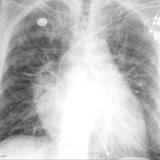

APE IABP

Date: 10/17/2010

Views: 3835